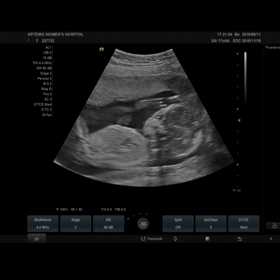

妊婦検診 13w0d 初の3D、4D動画